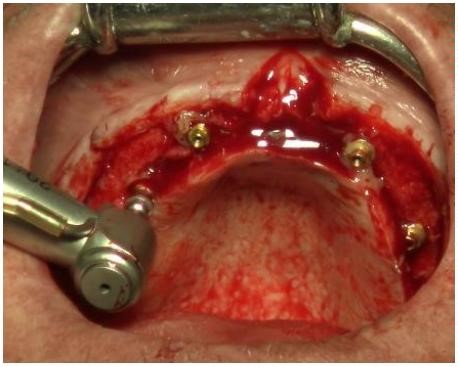

Una vez introducidos los implantes, se colocan los pilares transepiteliales (Figura 7) con pomada antibiótica TERRAMICINA® y se posicionan los pilares de carga inmediata sobre los que se pondrá la prótesis provisional superior. Por último se sutura con puntos simples utilizando una sutura reabsorbible de ácido poliglicólico (PGA) de 3/0 de grosor.

Para ferulizar los implantes colocados, se utilizó la técnica de a electrosoldadura intraoral, Por medio de dos barras de titanio grado II. (Figura 8)

Una vez colocados los implantes, se procede al posicionamiento de los pilares transepiteliales multiunit® inferiores , impregnados de nuevo en pomada antibiótica . Seguidamente se fijan los pilares de carga inmediata (Figura 9) y se sutura los tejidos con PGA de 3/0 de grosor con puntos simples.

Por último, usando las dos barras de titanio grado II de 1 mm y 1,5 mm de diámetro, se realiza la electrosoldadura intraoral. De esta manera conseguimos ferulizar la estructura y proteger los tejidos aportando estabilidad.